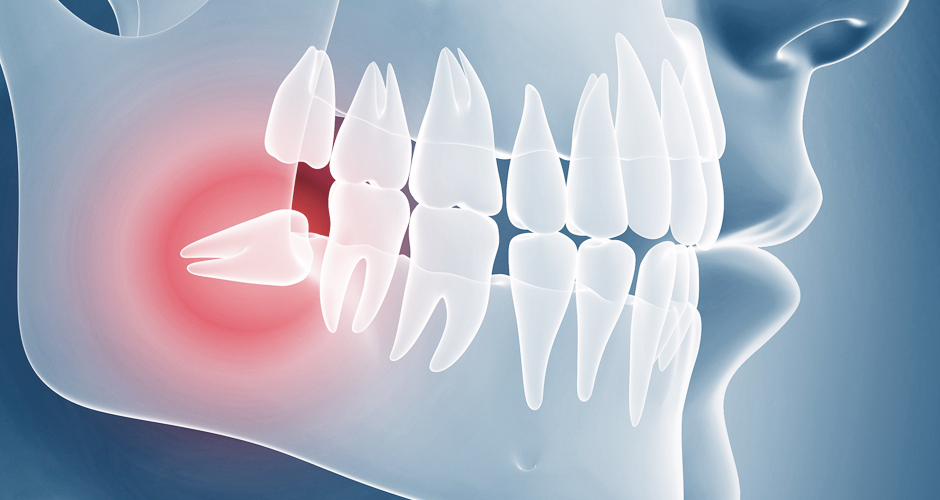

비정상적인 위치에 매복되어 자란 사랑니는

염증과 통증을 일으킬 수도 있으므로

발치하는 것이 좋습니다.

누워서 자란 사랑니의 경우

바로 앞의 어금니 뿌리를 압박해 염증을 일으키거나

턱뼈의 신경까지 손상시킬 수 있습니다.

사랑니와 어금니 사이에 음식물이 끼게 되어 충치 및 치주염 발생의 위험율이 높아집니다.